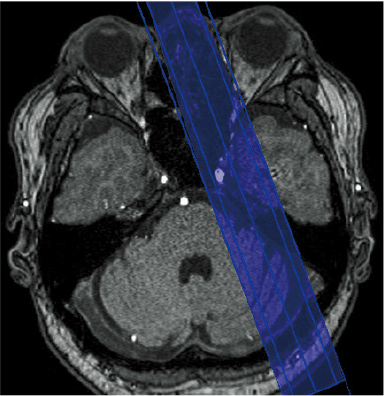

Pencil-beam type pre-saturation (BeamSat) pulses based on the application of local excitation are used in TOF imaging to selectively suppress some of the blood flow signals required for identification of the hemodynamics.

If imaging is conducted with BeamSat pulses specified for a target blood vessel, the flow signals of that vessel can be suppressed, and the dominant region can be identified. BeamSat pulses can be set to arbitrary positions and angles using a special GUI. The positions of BeamSat pulses can be set freely with respect to a target vessel.

In the BeamSat display, the continuous line represents a nearer part and the broken line a part farther than the scanogram; the hatched part is a cross-section between a BeamSat and a scanogram.

SAG cross-section: Position contacting nasal root/sella turcica

AX cross-section: Position contacting pyramid/clivus